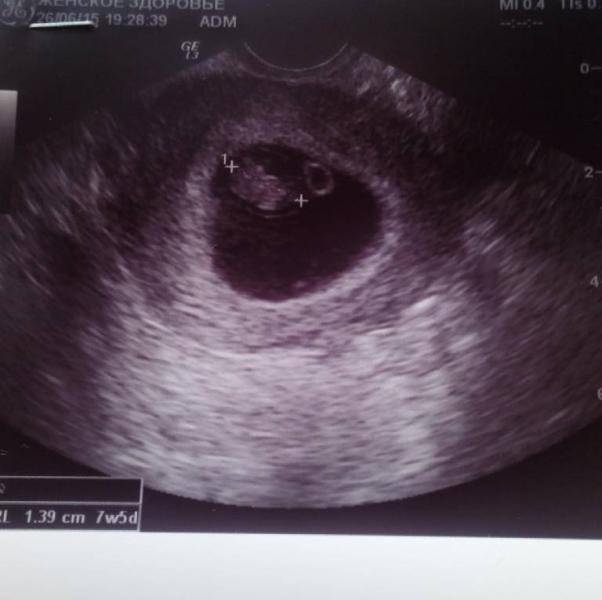

В ПНД (7.5нед) прошли все признаки Б кроме отвращения к еде. Прошла тошнота, подтягивания в животе, чувствит-ть груди. Я запаниковала. На птн уже было назначено платное УЗИ в клинике Здоровье Королев.

Ляля моя развивается чётко по сроку. Сердечко посмотрели ))))) НО поставили угрозу по УЗИ - плодное яйцо овальное в одной из проекций. Причин может быть море - от естественного отторжения маткой до "просто перенервничала". Назначила отдыхать, ...